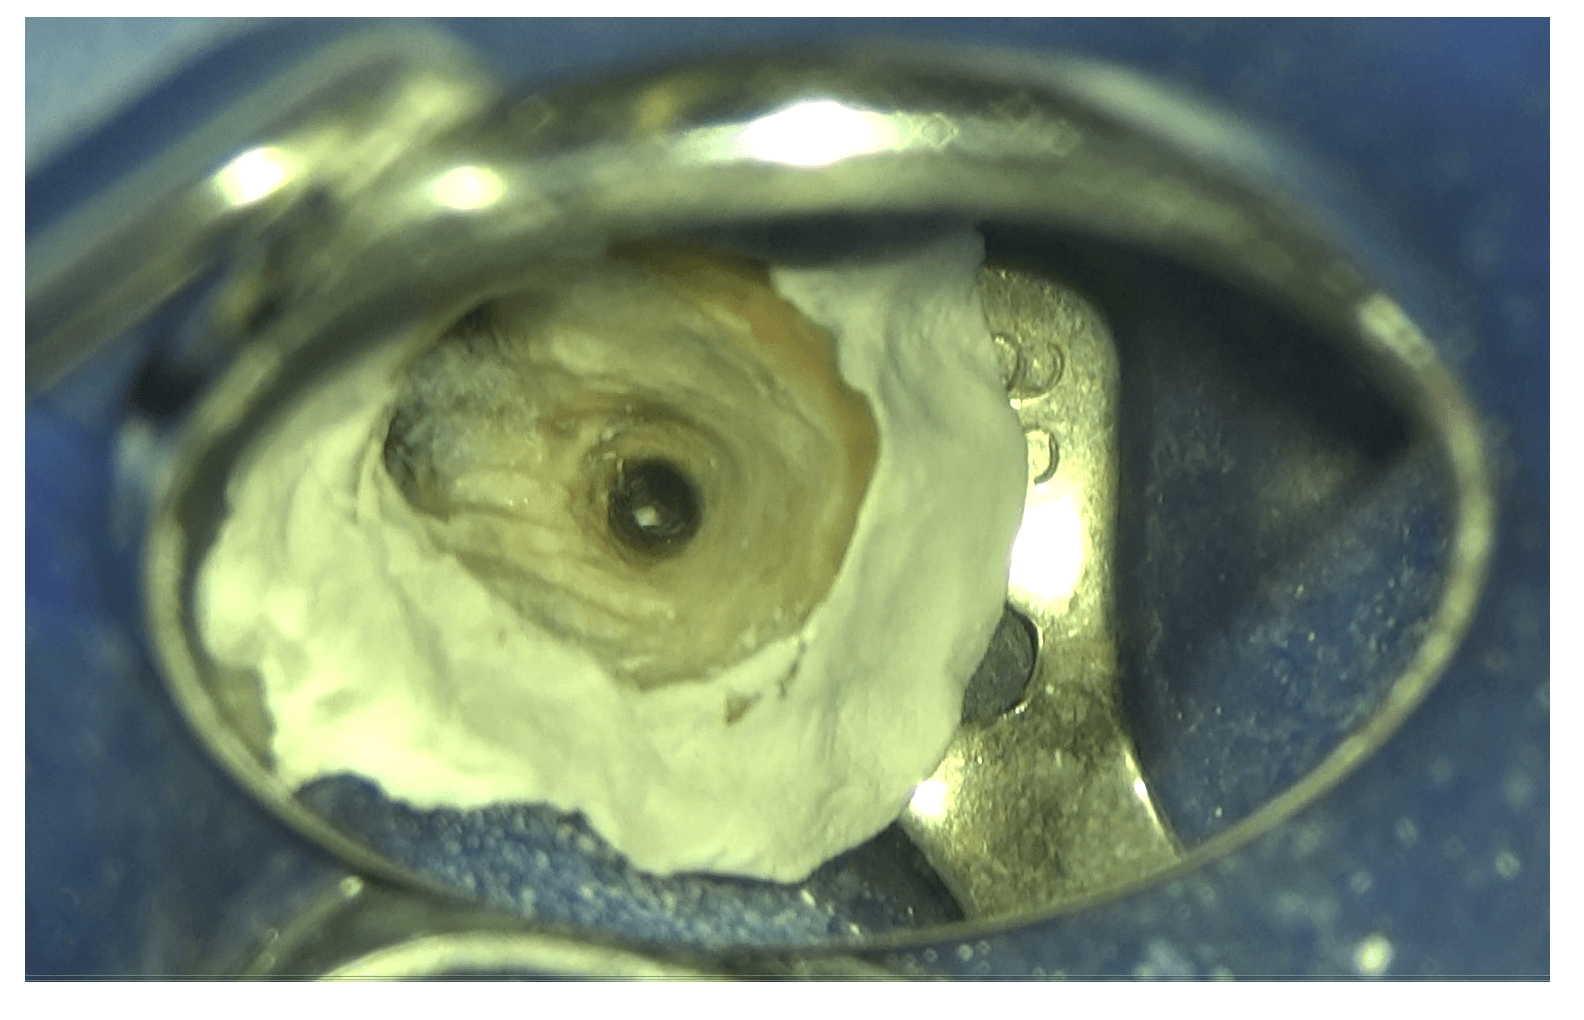

緊密に封鎖

こんにちは。 南館歯科クリニックの木村です。 精密根管治療の症例をご紹介します。 根管治療は細菌感染した根管内(神経の入っていた管)をいかに清潔にし、その清潔になった根管をきっちり封鎖することがとても…